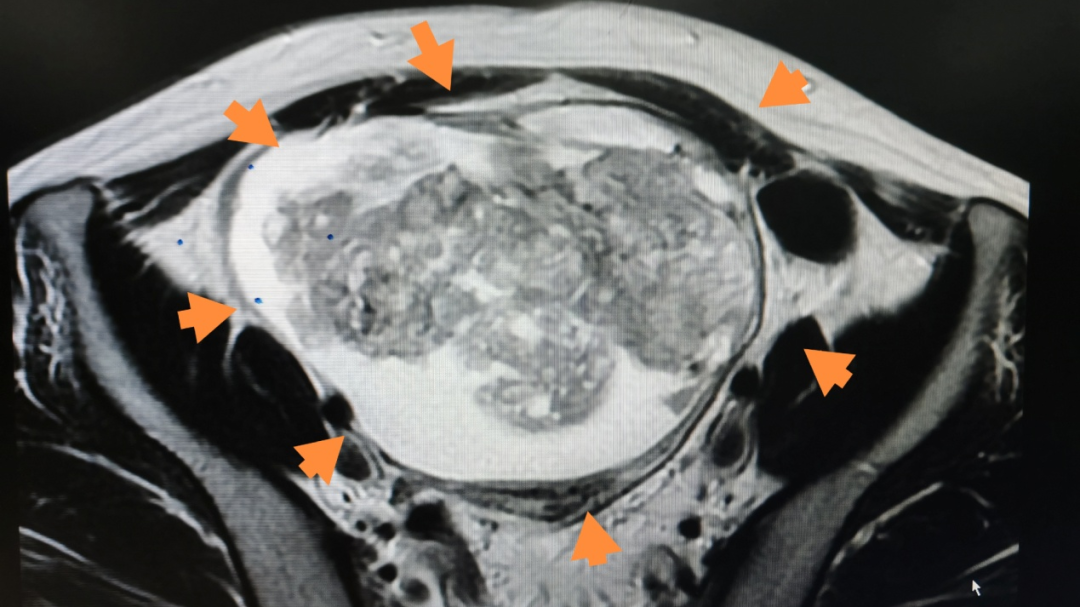

患者盆腔磁共振

腹部彩超检查显示,小娇盆腹腔内有巨大囊实性包块,盆腔磁共振进一步提示,该肿块性质待查,不排除畸胎瘤、粘液性囊腺瘤等可能,且伴有少量盆腔积液。

入院后,宁乡市人民医院知名专家、妇科主任刘青云主任医师经过细致地查体同时结合相关辅助检查结果考虑,该巨大肿物来源于卵巢,且不排除恶性可能,需紧急手术。术中探查发现腹腔内巨大囊实性肿物,快速病理提示为未成熟畸胎瘤,腹水中可见肿瘤细胞。